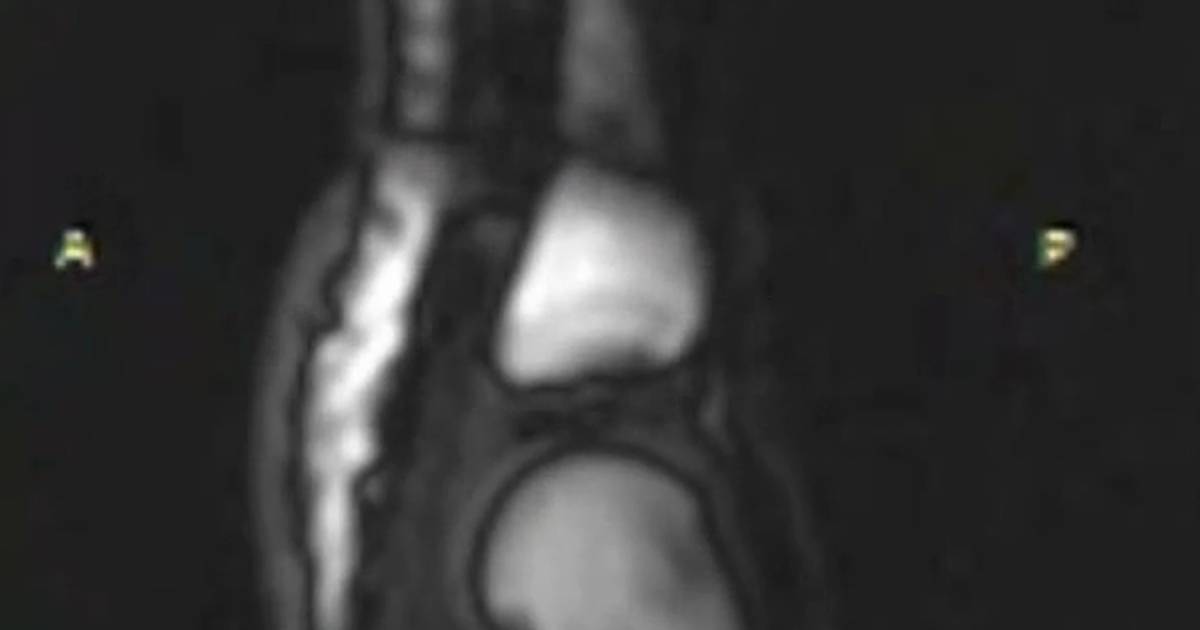

Het knakken van je gewrichten kan verschillende oorzaken hebben. Een veelvoorkomende oorzaak is het vrijkomen van lucht of gassen in het gewricht wanneer je het beweegt. Dit wordt ook wel het “cavitatie” fenomeen genoemd. Bij het bewegen van het gewricht wordt het drukverschil binnen het gewricht gecreëerd, waardoor de opgeloste gassen in het gewrichtsvloeistof vrijkomen en het geluid van het knakken produceren.

Er is geen bewijs dat het knakken van je gewrichten schadelijk is voor je kraakbeen. Kraakbeen is het stevige weefsel dat je gewrichten beschermt en ervoor zorgt dat ze soepel kunnen bewegen. Het knakken van je gewrichten heeft geen invloed op de gezondheid of slijtage van je kraakbeen.

Bij artrose kan het voorkomen dat de gewrichten een krakend geluid maken bij bewegen. Het krakende geluid wordt veroorzaakt doordat het kraakbeen en onderliggende bot van structuur veranderen. Het kraken is op zichzelf niet schadelijk of pijnlijk.Gelukkig is het knakken van je vingers helemaal niet slecht voor je, je krijgt er geen ontstekingen of versleten botten van. Maar het kan wel irriteren en zelfs pijn doen als je het heel vaak doet!

Bij artrose kan het voorkomen dat de gewrichten een krakend geluid maken bij het bewegen. Dit krakende geluid wordt veroorzaakt doordat het kraakbeen en het onderliggende bot van structuur veranderen. Hoewel het kraken an sich niet schadelijk of pijnlijk is, kan het wijzen op een onderliggende aandoening zoals artrose. Het kan ook betekenen dat het gewricht niet goed gesmeerd of stabiel is. Daarom is het altijd verstandig om bij aanhoudend kraken en eventuele pijnklachten een arts te raadplegen voor verder onderzoek en advies.